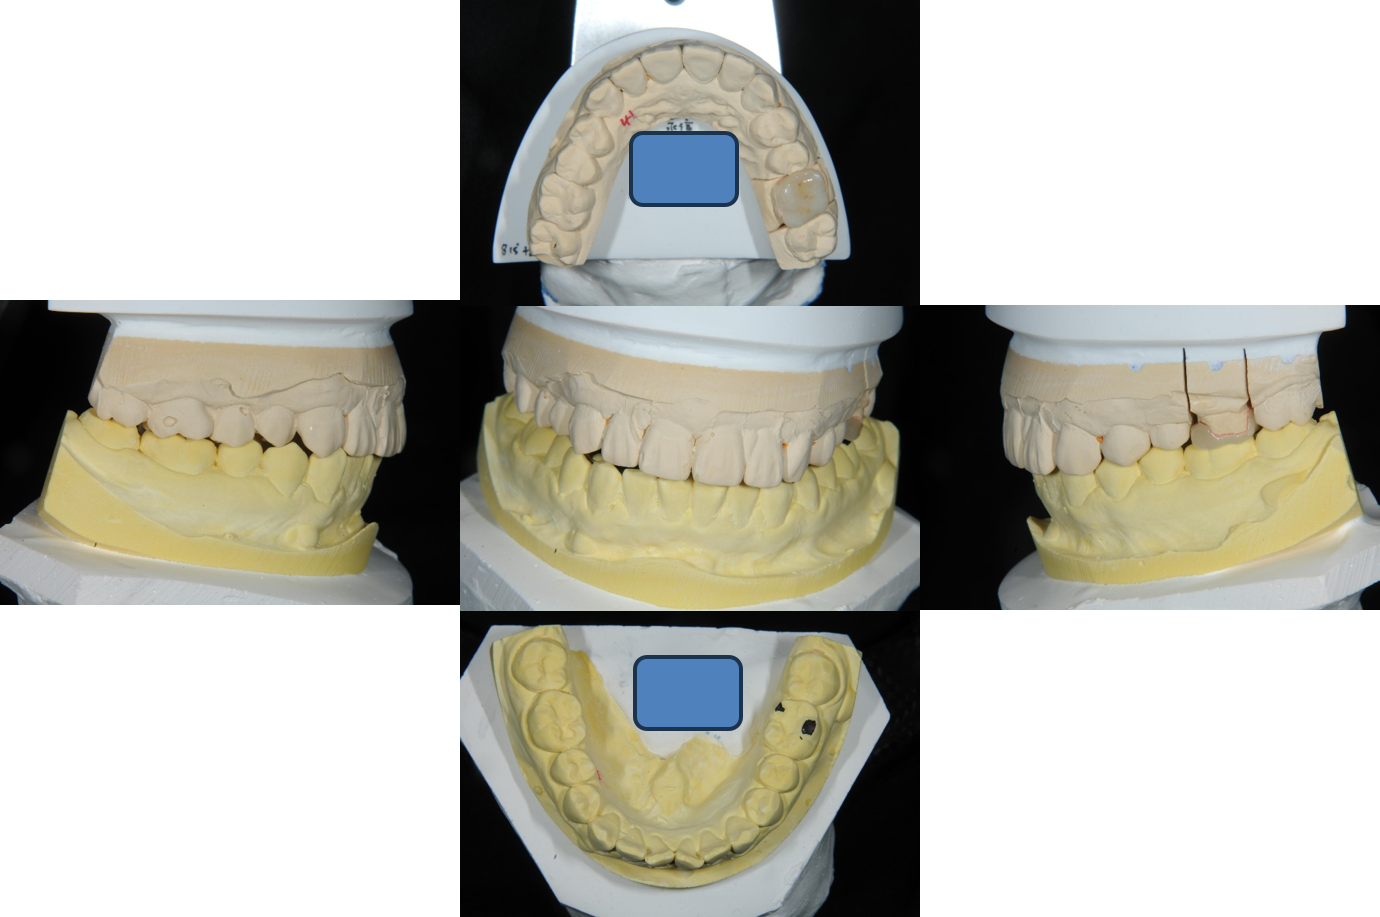

印模後,上咬合器

模型製作